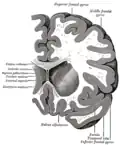

Section du cerveau montrant la surface supérieure du lobe temporal.